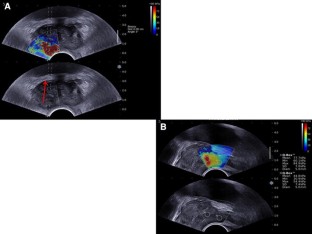

Shear wave imaging (SWI) is a new ultrasound technique whose application facilitates quantitative tissue elasticity assessment during transrectal ultrasound biopsies of the prostate gland. The aim of this study was to determine whether SWI quantitative data can differentiate between benign and malignant areas within prostate glands in men suspected of prostate cancer (PCa).

We conducted a protocol-based, prospective, prebiopsy quantitative SWI of prostate glands in 50 unscreened men suspected of prostate cancer between July 2011 and May 2012. The ultrasound image of whole prostate gland was arbitrarily divided into 12 zones for sampling biopsies, as is carried out in routine clinical practice. Each region was imaged by grey scale and SWI imaging techniques. Each region was further biopsied irrespective of findings of grey scale or SWI on ultrasound. Additional biopsies were taken if SWI abnormal area was felt to be outside of these 12 zones. Quantitative assessment of SWI abnormal areas was obtained in kilopascals (kPa) from abnormal regions shown by SWI and compared with histopathology. Sensitivity, specificity, positive and negative predictive values, and likelihood ratios were calculated for SWI (histopathology was a reference standard).

Fifty patients, with a mean age of 69 ± 6.2 years, were recruited into the study. Thirty-three (66 %) patients were diagnosed with PCa, while an additional 4 (8 %) had atypia in at least one of the 12 prostate biopsies. Thirteen (26 %) patients had a benign biopsy. Data analysed per core for SWI findings showed that for patients with PSA <20 μg/L, the sensitivity and specificity of SWI for PCa detection were 0.9 and 0.88, respectively, while in patients with PSA >20 μg/L, the sensitivity and specificity were 0.93 and 0.93, respectively. In addition, PCa had significantly higher stiffness values compared to benign tissues (p <0.05), with a trend toward stiffness differences in different Gleason grades.

SWI provides quantitative assessment of the prostatic tissues and, in our preliminary observation, provides better diagnostic accuracy than grey-scale ultrasound imaging.